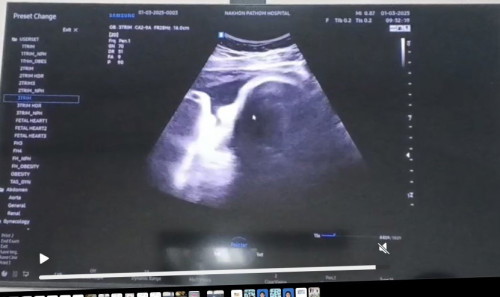

ช่วยดูให้หน่อยค่ะ ใช่จมูกหรือเปล่าค่ะ

พอดีไปซาวด์มาเห็นแบบนี้แต่หมอไม่ได้บอกค่ะ 37+2สัปดาห์ค่ะ

จมูกโด่งเชียว

จมูกน้องค่ะ